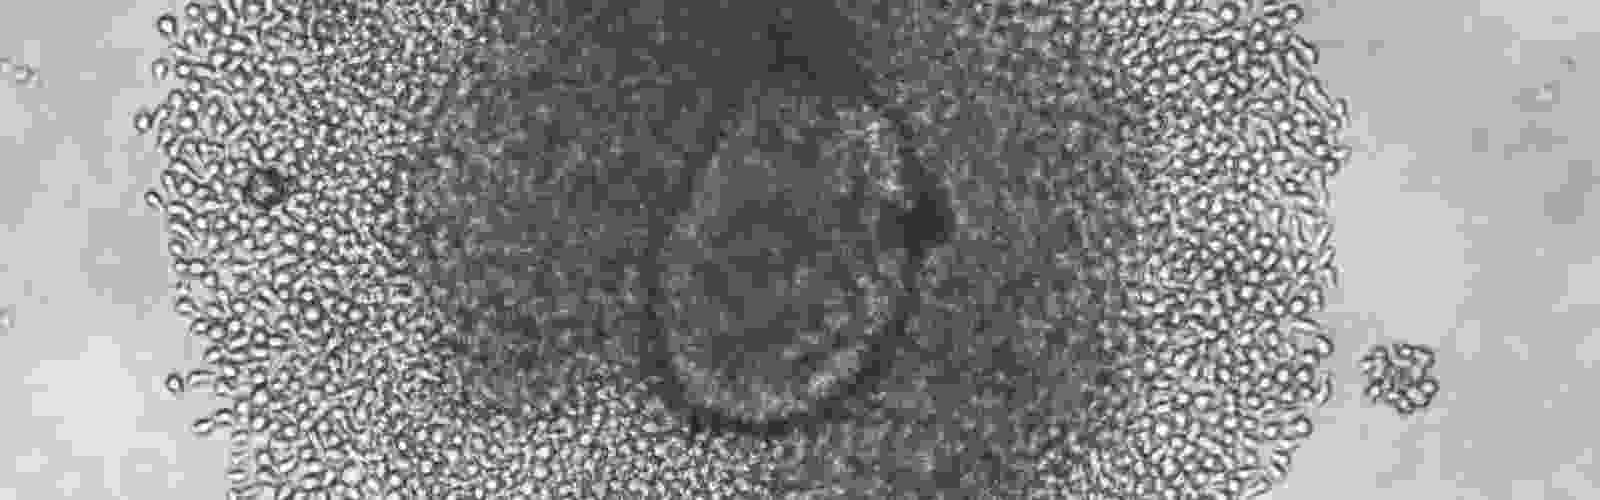

Kent Lab isolates immune cells from the islets of donors with T1D

In a highly collaborative effort, scientists at UMass Chan Medical School have isolated and characterized a large bank of live islet-infiltrating T cells directly from the islets of tissue donors with type 1 diabetes. The findings, published in Nature Medicine, have direct implications for the design of therapies and preventative strategies for those with type 1 diabetes and those at risk for developing it.

Using live islets from nine type 1 diabetic donors, Kent Lab sorted live lymphocytes by fluorescence activated cell sorting. They also used an improved tissue culture method they developed to grow lymphocytes from the islets. 236 T cell lines were derived from the islets, and they analyzed the function of 50 lines, discovering the specific reactivities of 18 lines. LEARN MORE